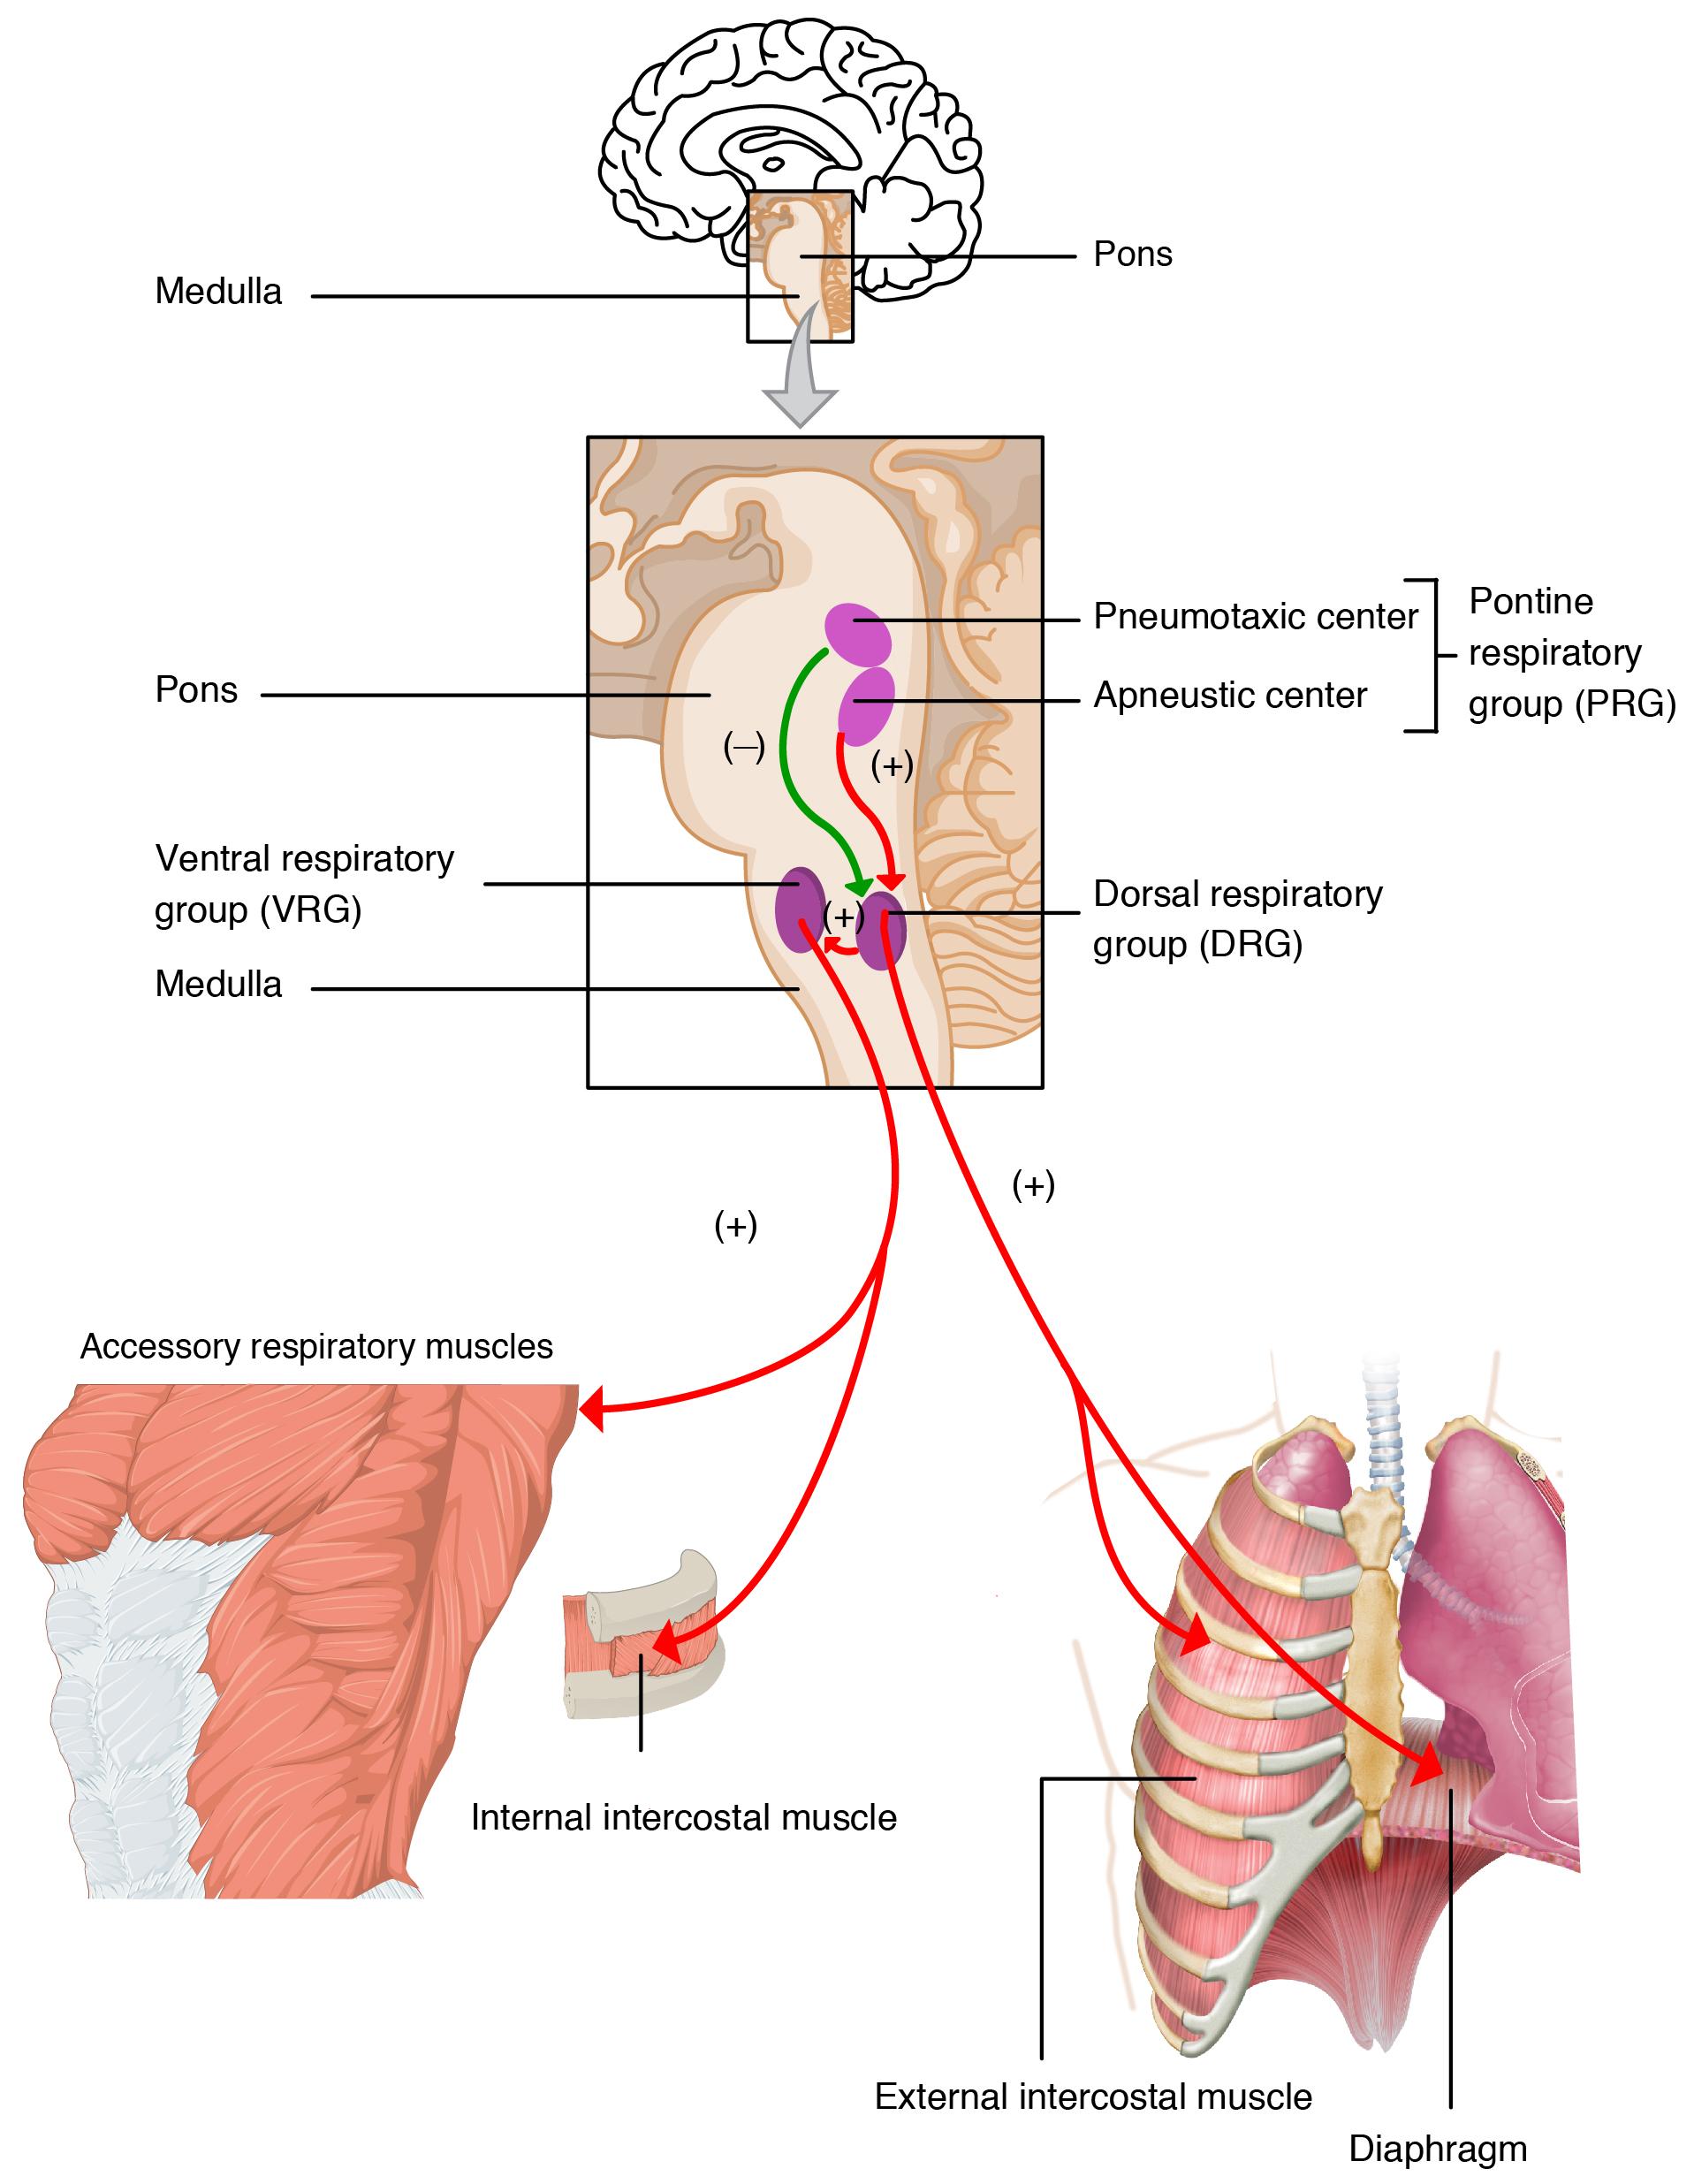

Figure 11 – Respiratory centres of the brain that control the respiratory rate and ventilation. The major brain centers involved in pulmonary ventilation are the medulla oblongata and the pontine respiratory group.